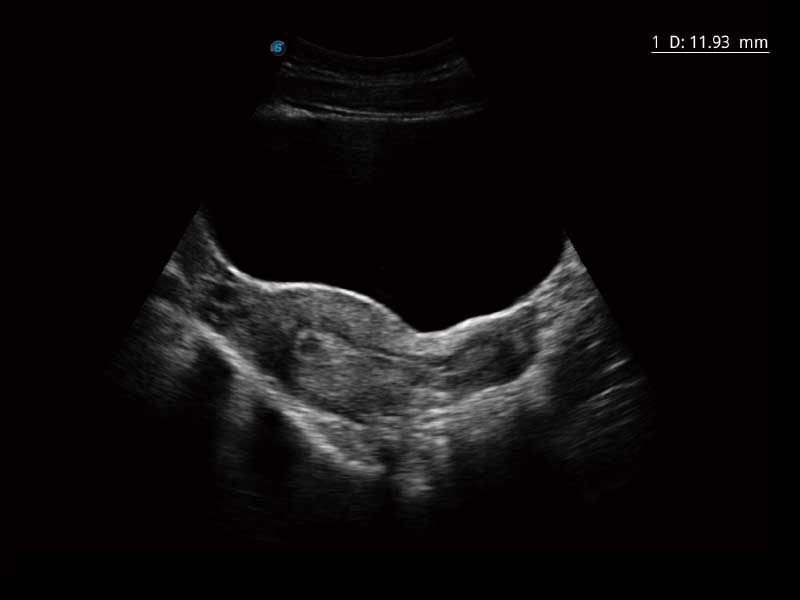

E2便携式彩色多普勒超声诊断系统采用专业的超声技术平台、高度集成化的硬件模块和结构设计、简便的操作流程、多探头接口设计,兼顾了优质图像、轻便机身以及台便两用的临床使用需求。

单键操作,可快速优化多个二维及多普勒图像参数,获得优异图像效果。